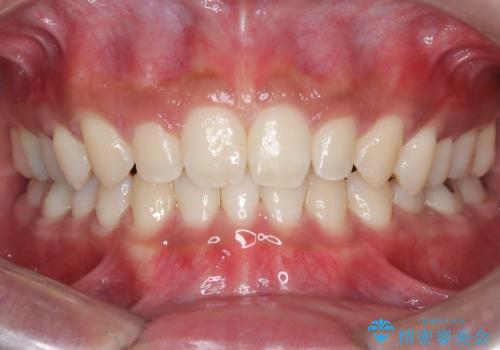

【インビザライン】空隙歯列の矯正

単純に前歯の隙間の閉鎖をしてしまうと、前歯に早期接触が生まれ、臼歯が噛まなくなってしまいます。適切な治療計画を立てることで、噛み合わせも良好な結果を得ることができました。

- 1年6ヶ月

- 治療回数